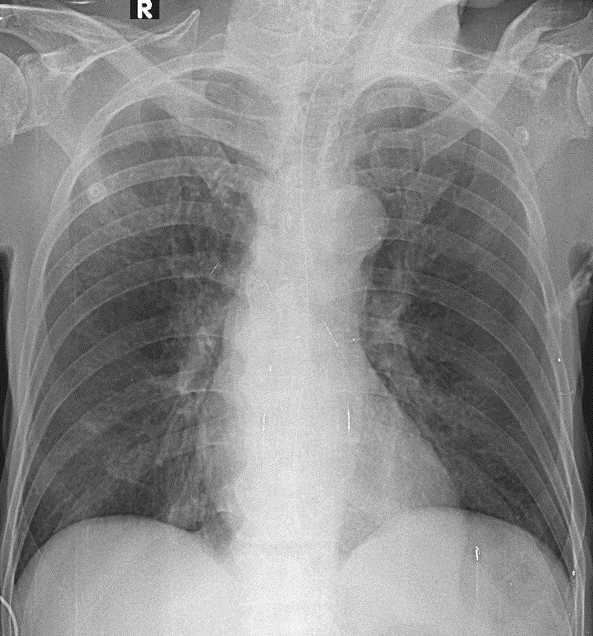

Hãy phân tích tình huống Nam 69 tuổi -CĐ: Suy hô hấp cấp đang ổn, Viêm phổi do Klebsiella pneumoniae esbl, ngưng thở khi ngủ

1-Thâm nhiễm mô kẻ thùy trên phổi (P) => VIÊM PHỔI